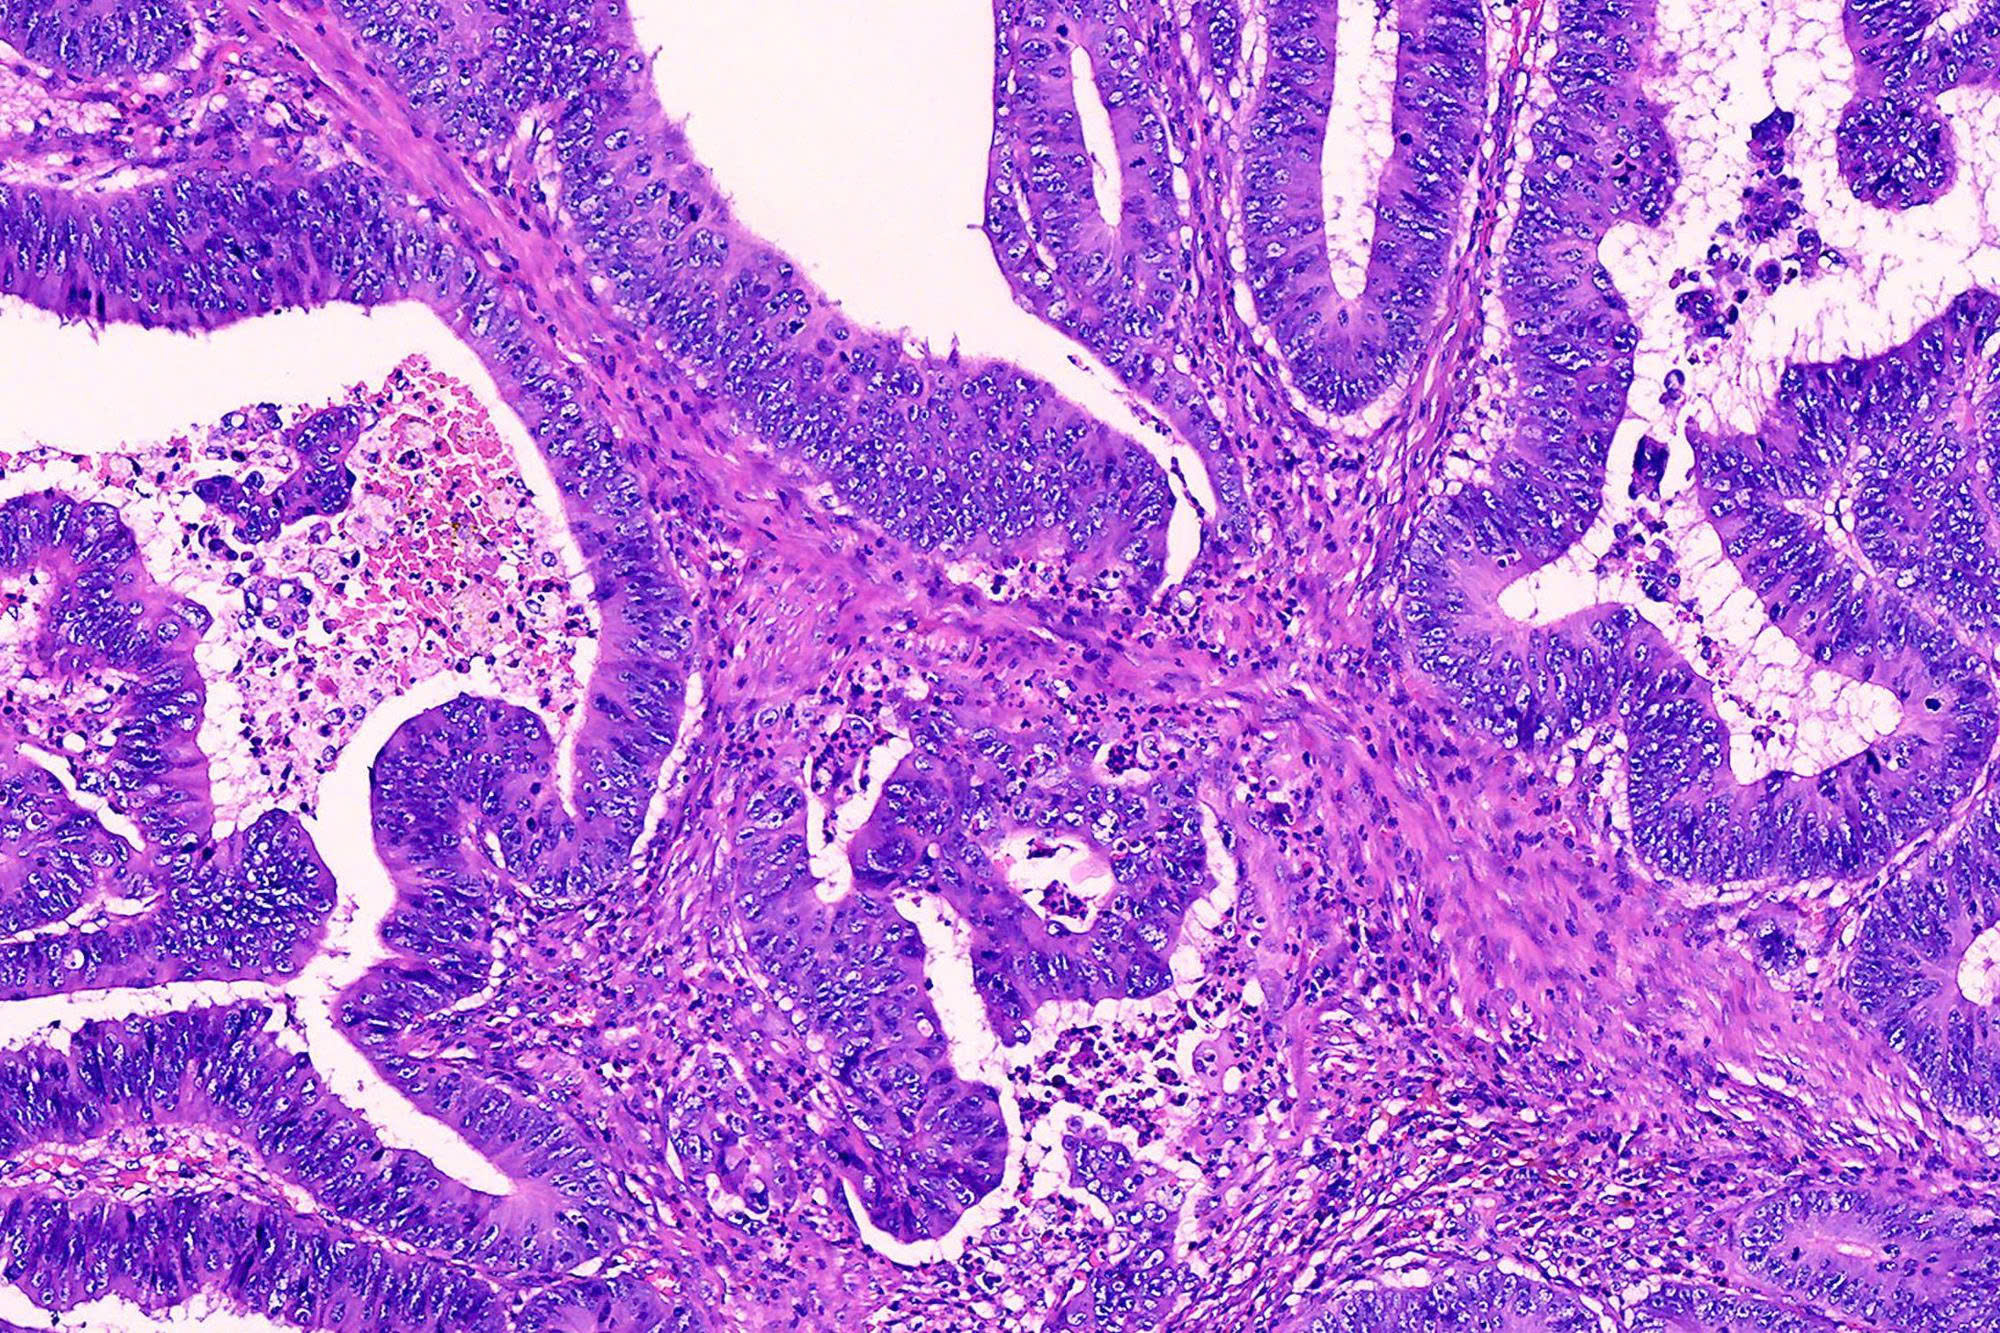

Về cơ bản, hóa mô miễn dịch là quá trình sử dụng kháng thể để phát hiện các kháng nguyên đặc hiệu trong các lát cắt mô.

• Cơ chế: Nếu tế bào có chứa protein (kháng nguyên) mà chúng ta đang tìm kiếm, kháng thể sẽ bám vào đó.

• Hiển thị: Thông qua một phản ứng hóa học tạo màu, các vị trí có sự kết hợp này sẽ hiện lên màu nâu hoặc đỏ dưới kính hiển vi, giúp bác sĩ quan sát được bằng mắt thường.

4. Nhuộm và đọc kết quả: Đây là bước đòi hỏi kinh nghiệm chuyên môn cao của bác sĩ giải phẫu bệnh để phân biệt giữa phản ứng dương tính thật và các tạp chất.